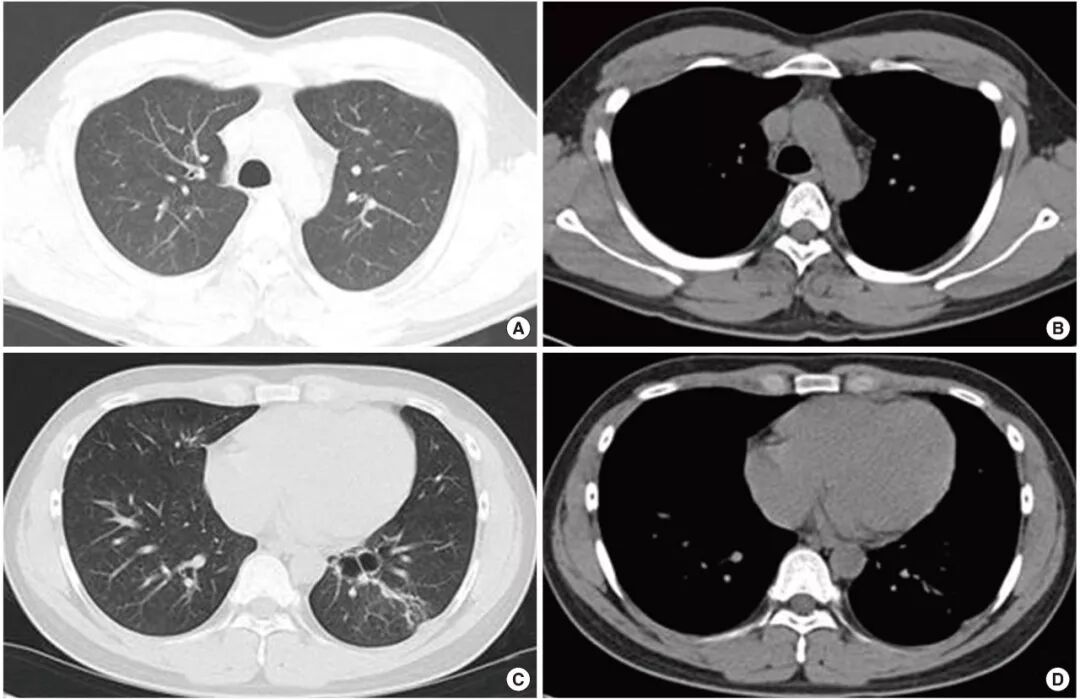

2.影像学特点  临床研究表明,重症腺病毒肺炎患儿肺部影像学表现特点如下:双肺见大片实变影,部分融合成片,边缘模糊;实变可呈节段性,多肺叶受累,可融合成大叶性实变,内可见支气管充气征;病变多以肺门为中心分布,而外带病变相对较少;部分病例以肺间质改变或间实质改变为主,表现为支气管血管相对增多、模糊,其间可见沿支气管分布的细小点片状影;部分病例在疾病后期出现闭塞性细支气管炎、慢性肺病表现,如马赛克征象、细支气管壁增厚、扩张等。以上影像学特点均提示重症腺病毒肺炎患儿肺部病变较重,易遗留肺部后遗症。

6个月后高分辨率CT随访发现肺纤维——轻度支气管扩张,左下叶基底段肺大泡。